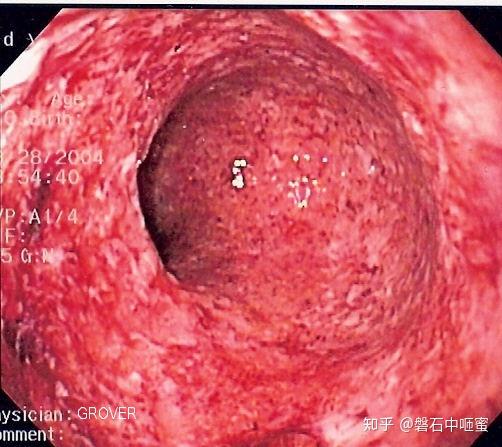

在我的工作中,经常会遇到一些需要仔细鉴别的疾病,其中克罗恩病就是一个让人头疼的问题。克罗恩病是一种慢性肠道疾病,症状复杂多样,容易与其他肠道疾病混淆,给患者带来不少困扰。

每当接到克罗恩病的病例,我总是倍感压力,因为这需要仔细的鉴别诊断。克罗恩病的症状包括腹痛、腹泻、体重减轻等,与一般的肠道疾病很容易混淆。但是,通过一系列的检查和综合分析,才能最终确定是否患有克罗恩病。